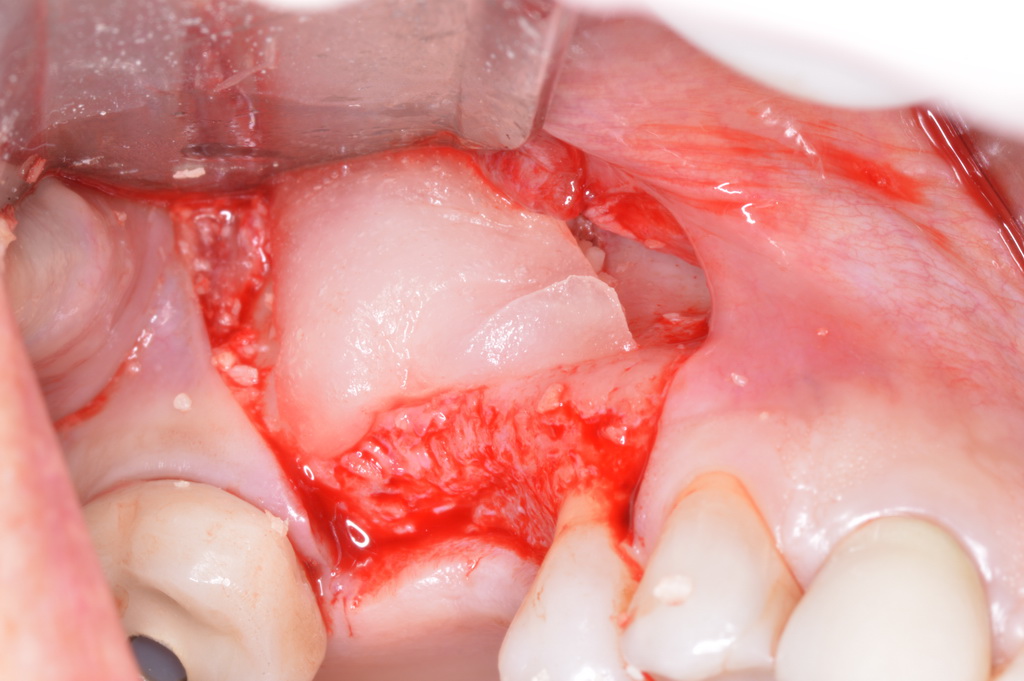

The patient had been referred for an implant consultation for the mandibular right canine. She had very deep probing depths on the lingual. When the flap was raised, a significant amount of subgingival calculus was seen as a local risk factor (Figure 18). However, she had no significant pathology to remove from the situation. Debridement was performed the same as in Case 3 with the rotary ultrasonic and manual instrumentation.

The defect was obturated with mineralized freeze-dried bone and hydrated with platelet-derived growth factor. As with any growth factor, when implementing it clinically, all growth factors require a carrier to bring that growth factor to the desired site, which do not elicit an inflammatory response. In this situation, it is the mineralized freeze-dried bone allograft. This combination was demonstrated by Rosen et al8 to be efficacious in treating intrabony defects. A biologic approach was taken both in terms of the graft and membrane (Figure 19). Primary closure was achieved.

Subgingival calculus and severe bone loss.

Figure 18

An amnion-chorion membrane adapted over the bone graft.

Figure 19